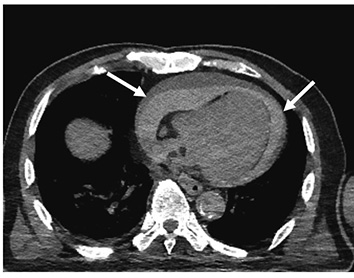

死亡時画像診断(Autopsy imaging)におけるチェックシートの